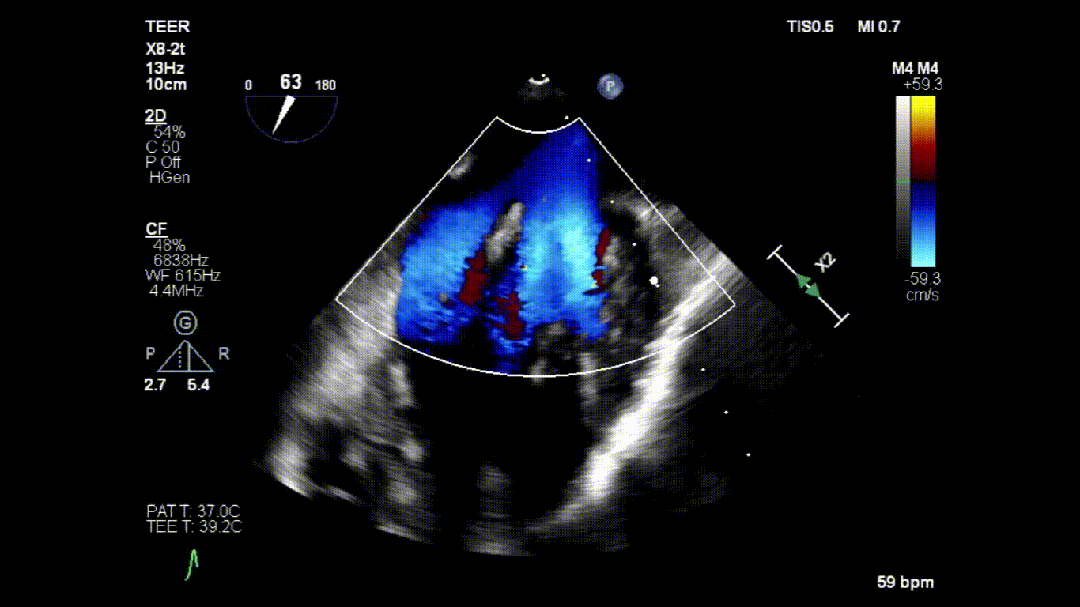

本次培训的“重头戏”—— 两台高难度 TEER 手术沉浸式观摩,将培训氛围推向高潮。手术病例分别为 “P2 宽大脱垂病变” 与 “早期 Barlow 病变”,由厦门大学心血管病医院团队与浙江大学附属邵逸夫医院团队协同完成。术中,专家团队操作精准、配合默契,不仅完美展现了 TEER 技术在复杂病例中的应用优势,更通过实时讲解,让学员直观掌握手术关键步骤、解剖评估要点与应急处理思路。

病例2: